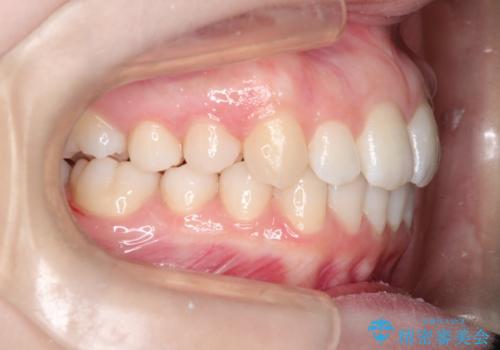

[インビザライン ライト] 短期間(3.5ヶ月)で終わるマウスピース矯正

![[インビザライン ライト] 短期間(3.5ヶ月)で終わるマウスピース矯正の症例 治療後](https://seimitsushinbi.jp/wp/wp-content/uploads/2020/02/2f36cdf472a802b537022ae239b8cb6b-500x350.jpg?v=1580813669)